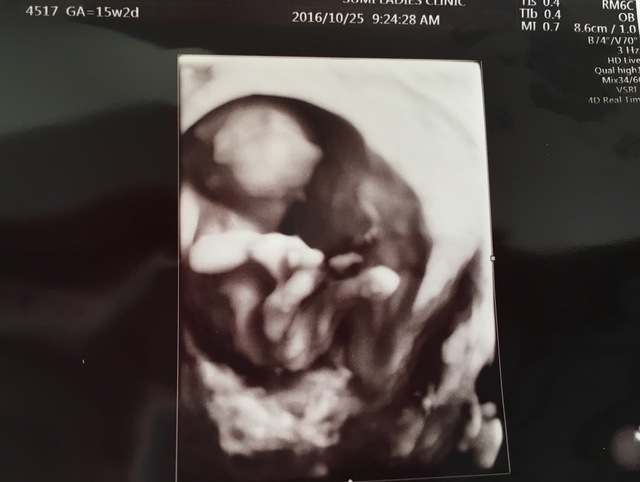

15週3日(15w3d・男の子)|kaaaa さん(25歳)

エコー写真撮影時のエピソード:

第二子にして初めて4Dエコーを貰った時のものです。まだ4ヶ月で胎動もなく今まで3Dエコーではぼんやりとした輪郭しか分からなかったのにちゃんと人の形になってる!!と感動しました。

主人も今まではエコーを見ても「ふーん」ぐらいの素っ気ない返事でしたが、これには喜んでくれました!やっぱり見やすい方が実感湧くのでしょうか。(笑)

上の子もまだ1歳でしたが、この頃から「ママのお腹には赤ちゃんがいるんだよ~~。こんなして寝んねしてるよ~~。」と話していました。毎日お腹をさすってくれて産まれる前からお姉ちゃんをしてくれています。